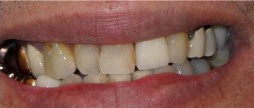

Working cast

Intraoral photograph

- Missing 11/ unacceptable esthetics

- The first treatment that was offered was making of his flipper denture as he was psychologically distressed without his front tooth which negatively affected his quality of life

- Once the patient was satisfied with the flipper denture and denture hygiene instructions were given, I visually demonstrated proper brushing techniques with dental care model and large toothbrush used for educational purposes